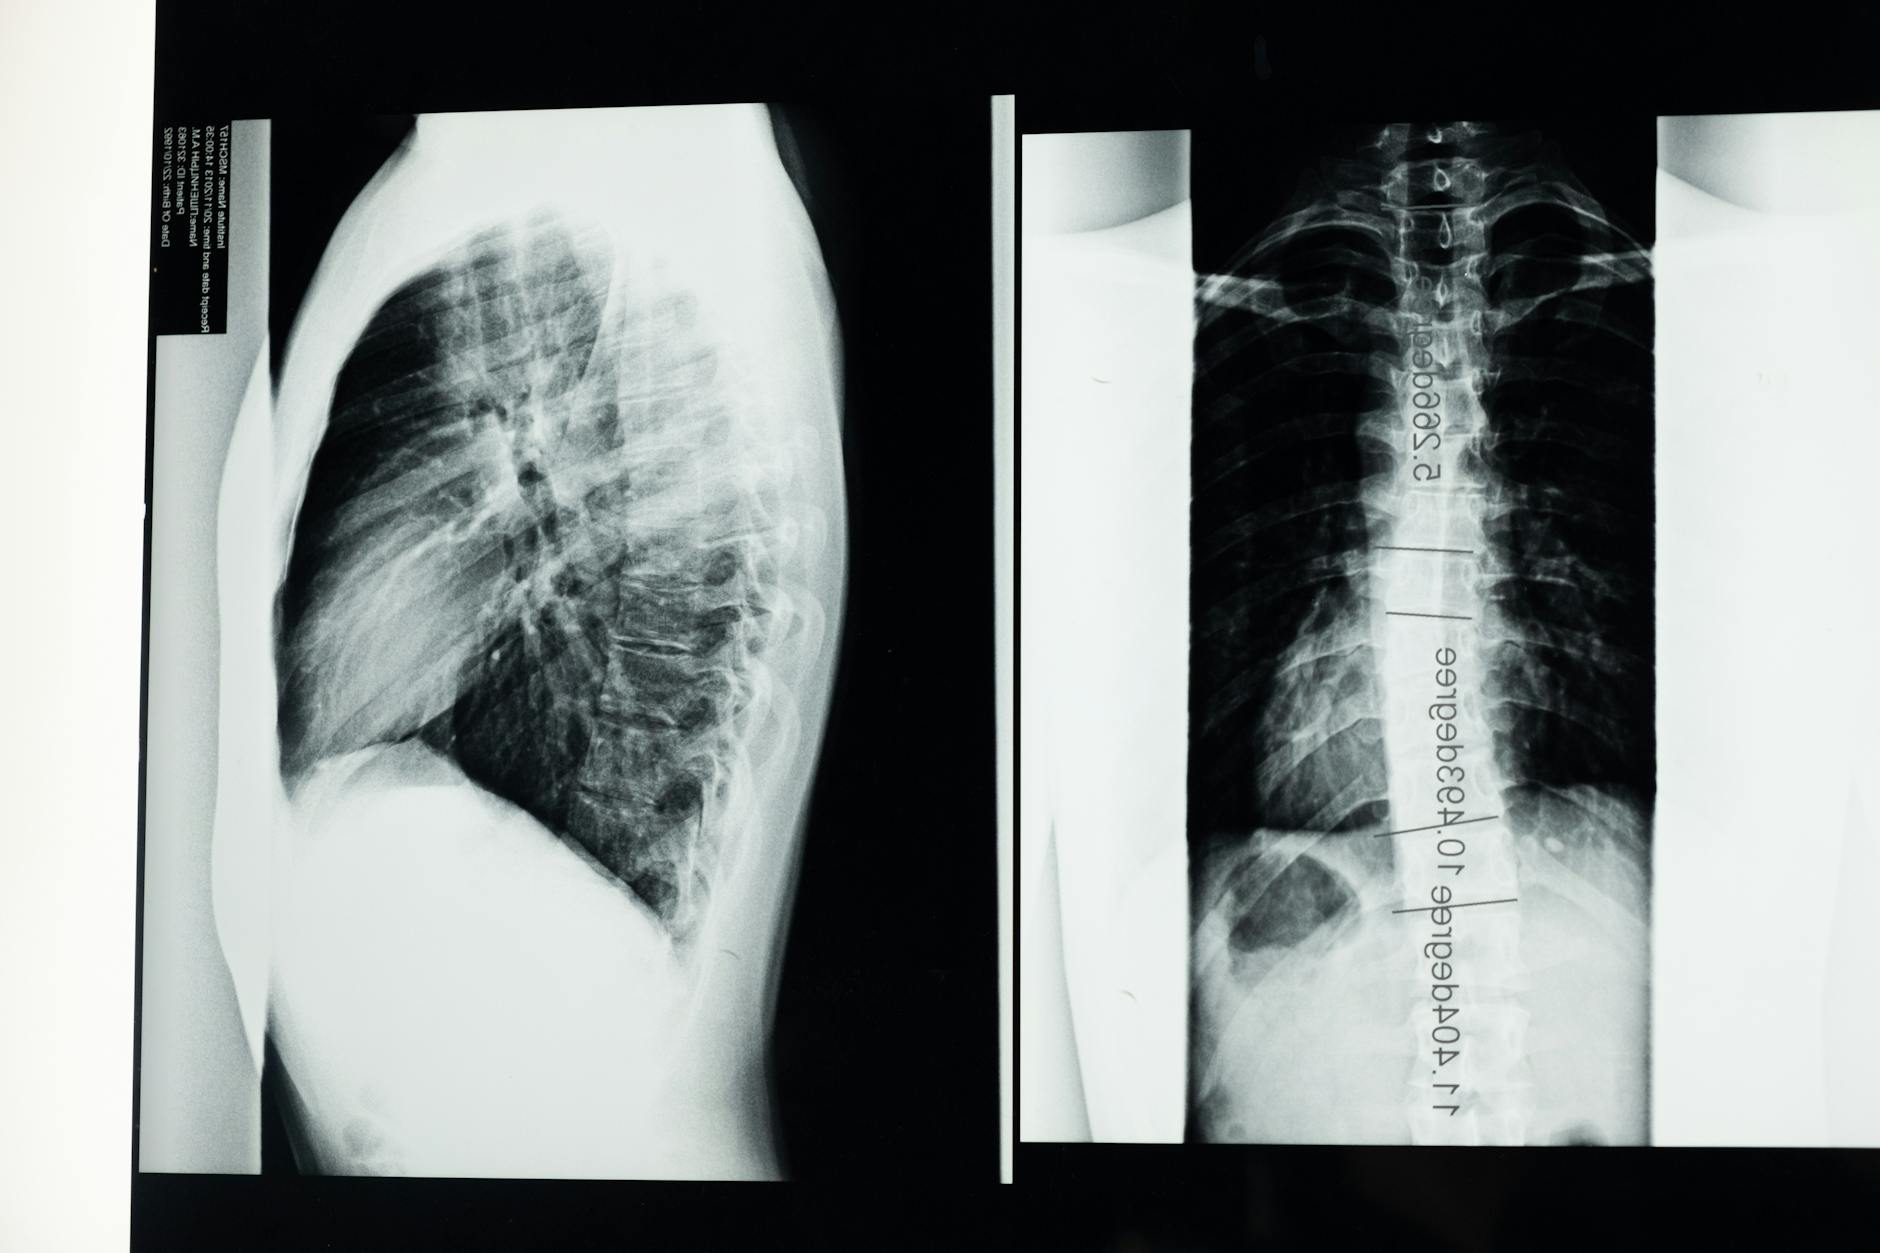

A thorough evaluation for thoracic spine lesions begins with a careful history and a focused physical examination. Your clinician will ask about the onset, duration, and character of symptoms, any related medical conditions, and how activities influence pain. The physical exam typically includes assessment of spinal range of motion, palpation for tenderness, and a neurological check for sensation, strength, and reflexes along the trunk and legs. This helps identify whether a lesion may be compressing neural structures or causing other dysfunction.

Imaging and laboratory tests are considered based on findings from the history and exam. A common sequence may involve targeted imaging to clarify anatomy and guide decisions about treatment options. Throughout the process, shared decision‑making is emphasized: clinicians discuss potential diagnoses, the risks and benefits of tests and treatments, and align plans with patient goals and values. It is important to acknowledge that imaging can reveal incidental findings that may not explain symptoms; decisions about management should reflect the overall clinical picture and preferences of the patient.